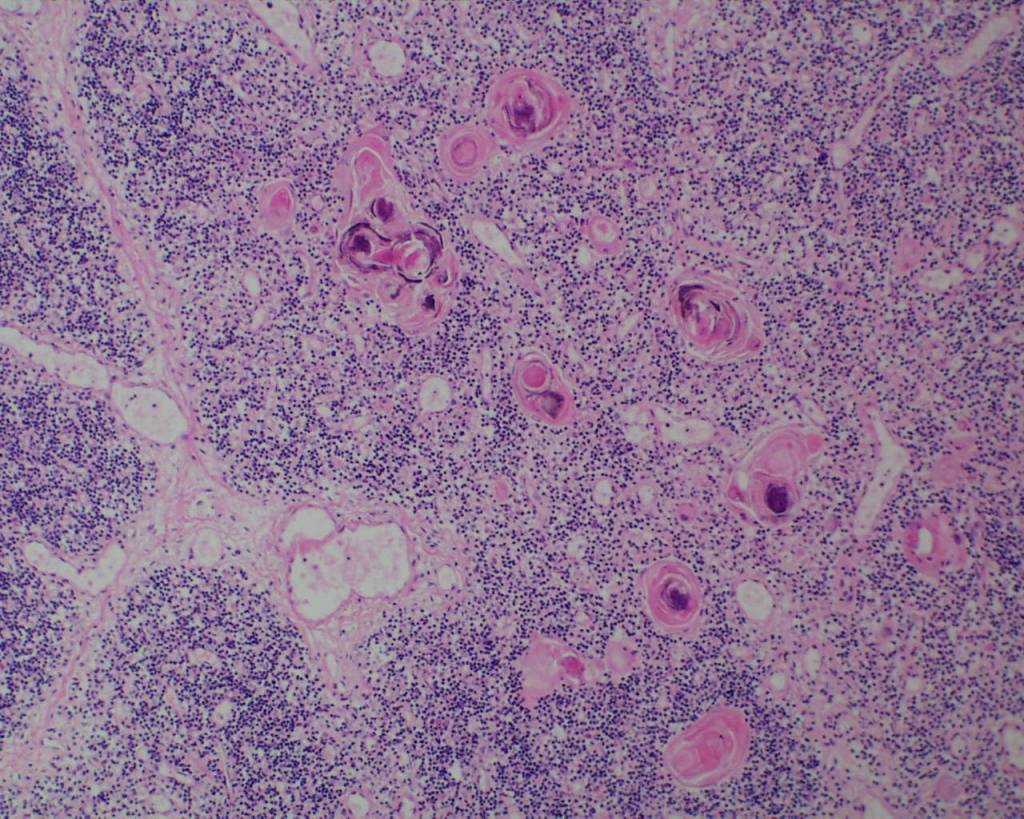

In the thymus at younger gestation, Hassall corpuscles may not be evident although small clusters of epithelial cells may be found (Fig 18).

Hassall corpuscles become prominent by 28 weeks of gestation[23]. In trisomy 21, they may be quite large and cystic (Fig 19).

A complete lack of Hassall corpuscles is evidence of an inherited immune deficiency. The thymus most likely will be small. The lack of thymic Hassall corpuscles is associated with immune deficiency in postnatal life. Such a finding prenatally may be associated with a molecular diagnosis of a specific immune deficiency. Thymic dysplasia is diagnosed only if the medullary epithelial component is absent. Hypoplastic thymuses that are not involuted nor dysplastic may be part of a wider malformation syndrome such as Di George (deletion of 22q1.2) that have Hassall corpuscles may still be associated with a T-cell deficiency (Fig 20,21).